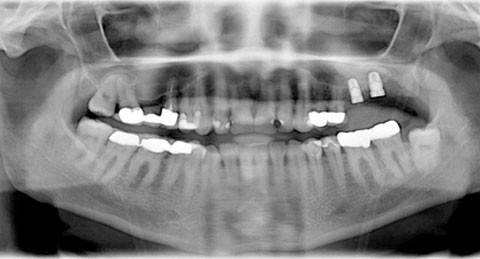

Die zu Behandlungsbeginn 42-jährige Patientin stellte sich ohne allgemeinmedizinische anamnestische Auffälligkeiten zur Implantatplanung in Regiones 26 und 27 vor. Grund hierfür war eine zukünftig zu erwartende einseitige Freiendsituation. Es fanden sich ein nicht erhaltungswürdiger Zahn 26 und ein teilretinierter, verlagerter Zahn 28. Der Zahn 27 war ca. sieben Jahre zuvor entfernt worden. In Regio 27 fand sich ein stark atrophischer Kieferkamm in vertikaler und orovestibulärer Richtung. Es bestanden außerdem starke Schlifffacetten aufgrund Bruxismus, eine Eckzahnführung und teilretinierte und verlagerte Zähne 28 und 38. Trotz intensiver Aufklärung wollte die Patientin diese Zähne nicht entfernen lassen. Der Unterkiefer links war durch zwei verblockte Kronen 36 und 37 versorgt. Die Patientin berichtete von einer Nasenscheidewandkorrektur im Jahr 2006, bei der zeitgleich eine Zyste aus dem rechten Sinus maxillaris entfernt wurde. Der linke Sinus maxillaris war nicht voroperiert und bisher beschwerdefrei (Abb. 1.)

Es wurden eine digitale Panoramaschichtaufnahme mit Röntgenmesskugel sowie eine Nasennebenhöhlenaufnahme zur genaueren Planung angefertigt. Zusätzlich wurden Situationsmodelle angefertigt (Abb. 2 und 3).

Vor dem weiteren Therapiebeginn wurden als radiologische Aufnahme ein digitales Orthopantomogramm und eine Nasennebenhöhlenaufnahme angefertigt. Dies diente zur Beurteilung der Resthöhe des Alveolarkammes und dem Ausschluss von akuten oder chronischen Erkrankungen, wie z.B. akuter Sinusitis maxillaris, Polypen, Tumoren, Wurzelresten, apikalen Prozessen oder Zysten im Oberkiefer (Abb. 2 und 3).